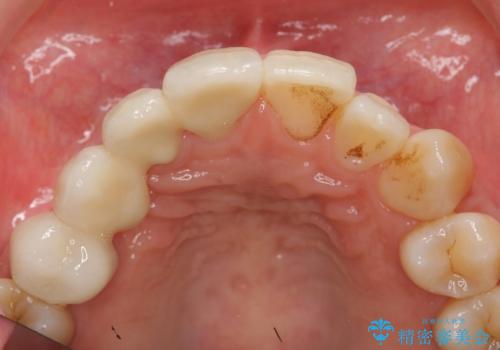

右上④3②①ブリッジの設計としました。

結果、非常に満足していただきました。

- 44万円 (ジルコニアクラウンスタンダード 10万円×4本 仮歯1万円×4本)費用は治療当時の料金となります

右上2番単独の支台歯では不足のため、右上12とも支台歯にしています。